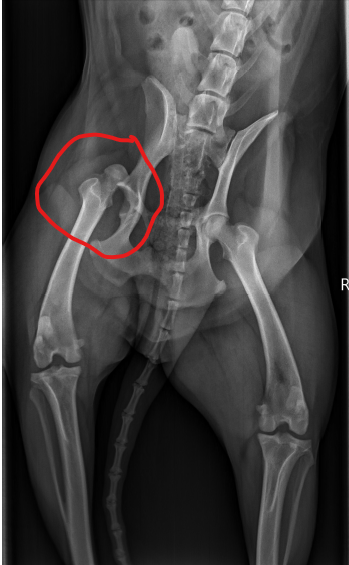

Kolia erlitt einen Sturz aus hoher Höhe und landet sehr unglücklich auf seiner Hüfte. Die Folge war eine traumatisch bedingte einseitige Femurkopfluxation, d.h. soviel wie der Oberschenkelkopf (Femurkopf) ist aus der Gelenkpfanne (Acetabulum) gesprungen. Eine eher seltene und wie man sich vorstellen kann eine sehr schmerzhafte Angelegenheit. Auf dem Röntgenbild sah das dramatischerweise dann so aus:

Man kann hier sehr gut sehen, dass der Oberschenkelkopf neben der Pfanne liegt.